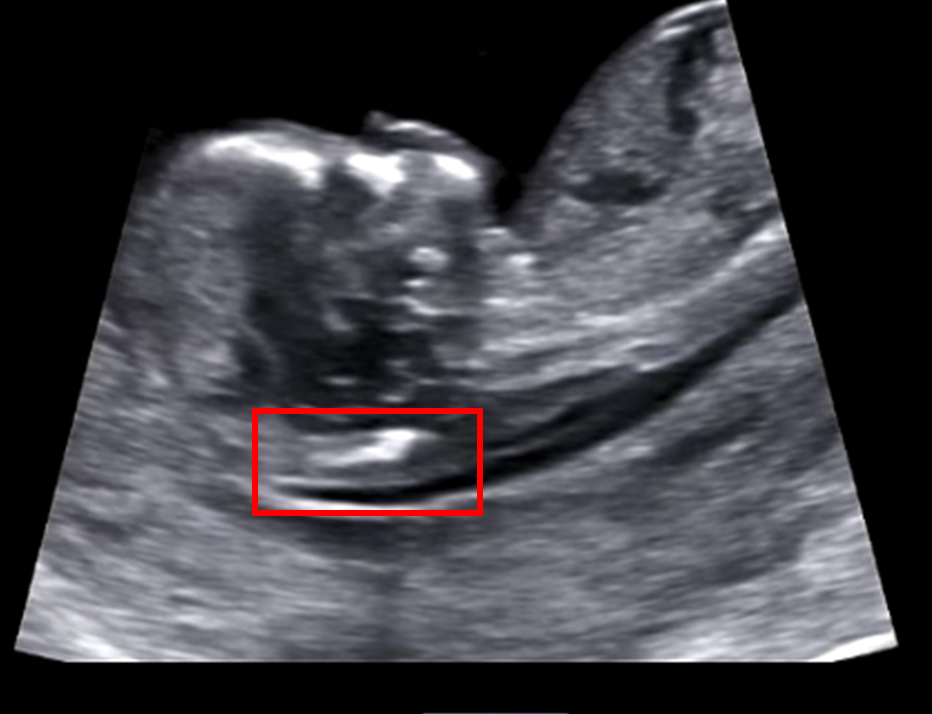

임신 초기 (12~13주)에 시행하는 초음파는 태아 목덜미 검사로 염색체 이상에 대한 선별 검사다. 목덜미 투명대 두께의 증가는 여러 가지 구조이상과 연관이 있으며 증가된 이유로는 다운 증후군과 같은 염색체 이상의 가능성과 심장기형 및 흉곽 기형과 같은 태아의 구조적 이상 유무 등이 있을 수 있어 정밀 초음파로 문제 여부를 확인한다고 하여 검진을 받기 위해 이전과 같이 일찍 퇴근해 호띵엄마와 병원에 갔다. 그동안 영상으로만 봤으나 직접 호띵엄마와 함께 진료실에서 초음파를 보니 호띵이의 아빠가 된다는 게 더 실감이 났다. 뱃속의 호띵이는 10분간의 진료 동안 정말 쉴 새 없이 움직였다. 그 모습을 보고 있자니 웃음이 났다. 얼마나 빨리 나오고 싶으면 벌써부터 가만히 있지를 못하고 계속 움직이다니! 아래는 영상의 일부를 GIF로 변환해 본 것인데 움짤 속 호띵이는 부끄러운지 손으로 얼굴을 가리고 있다.

정밀초음파 속 호띵이는 귀도 잘 크고 있고 코뼈도 정상적으로 잘 크고 있는 것으로 보였다. 그리고 손과 발을 쉴 새 없이 움직이는 것을 보고 운동량도 상당하는 것을 알 수 있었다. 정밀 초음파를 마치고 담당 의사 선생님의 진단 결과를 기다렸다. 담당 의사 선생님이 워낙 친절하셔서 그런지 갈 때마다 대기환자가 정말 많다. 30분가량의 기다림 후 의사 선생님의 검진 결과를 받게 되었다. 호띵엄마에게 진단 내용을 전달받았는데 태아 목둘레가 2.5mm 이상이면 문제가 될 수 있다고 하였으나 우리 호띵이는 1.4mm로 문제없이 잘 크고 있음을 확인하였다. 12주 차 검진으로는 성별은 알 수 없고 1개월 후에 2차 정밀초음파 때 알 수 있다고 하였다. 호띵이가 어떤 성별이든 건강하게 태어나 주길 바란다.